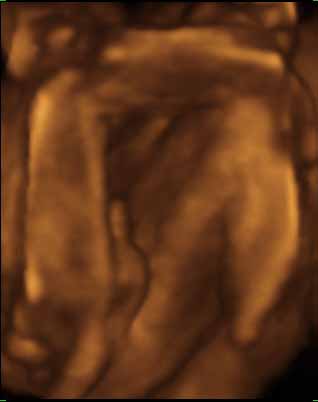

Tegnapi uhu: minden rendben - ez már nem megy olyan csoda számba... na jó, azért persze az. A doki kedves volt, úgy látszikmegérte az eddig belefektetett pénzt. Kikérdezte h mikor kell bemenni a koriba... Marcell baba feje 67mm, lábszára pedig 48. kérdeztem h mekkora lehet a súlya, azt mondta hogy azt sose akarjam tudni...